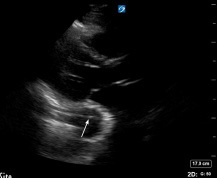

However, there are findings on TTE that would raise concerns for aortic dissection, particularly if done using point-of-care ultrasound (POCUS). Detection of aortic intimal flap (indicating the intimal tear), aortic wall thickening or dilatation greater than 40 mm, new major aortic regurgitation that can include cusp prolapse, or pericardial effusion (especially with echogenic material suggestive of hemopericardium) all are findings on TTE that are concerning for aortic dissection. Dilatation of the aortic root also can be seen in type A dissection, and dilation of 4.5 cm or more is sensitive for dissection but is not specific.1,13,31 (See Figures 5 and 6.) Observing these abnormalities on TTE should prompt immediate CTA of the aorta and consultation with surgical colleagues.8

Figure 5. Cardiac POCUS Parasternal Long Axis View Showing Intimal Flap |

![]() |

POCUS: point of care ultrasound Image courtesy of Daniel Migliaccio, MD |